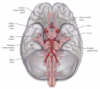

ID the structures on ventral brainstem

A

How well did you know this?